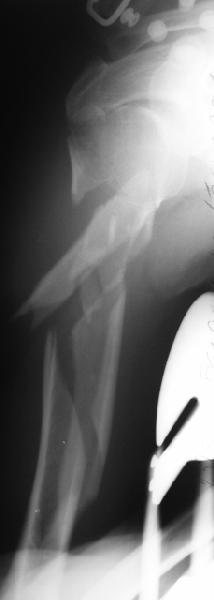

Well, to date he is still on abduction splint with traction applied to a wire placed through the olecranon. Images attached. The acetabulum

was ORIFed. The humerus is still discussing...

The views you now show demonstrate an extra articular fracture with good alignment on the AP, and some displacement on the lateral.

This should be able to be managed with adjustment of the traction.